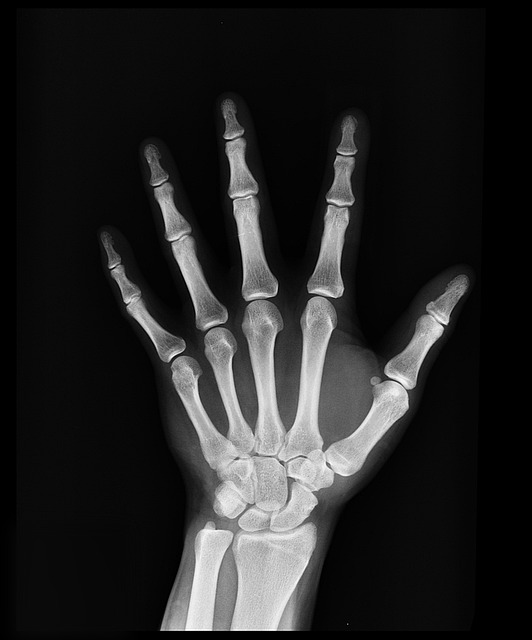

손가락의 뼈와 뼈는 관절로 이어져 있고, 뼈 끝부분에는 연골이 있고, 연골과 연골사이에는 '관절 주머니'라는 것이 연고을 받치고 있습니다.

이 관절 주머니는 무색의 알칼리성 액체로 차 있으며, 이 액체는 관절을 부드럽게 움직이게 해 주고 뼈 사이의 마찰을 없해주는 역할을 합니다.

손가락을 당기거나 힘을 주어 구부리면 이 액체가 차 있는 관절 주머니도 같이 잡아당겨지게 되는데, 이때 '공동현상'이 발생하게 됩니다.